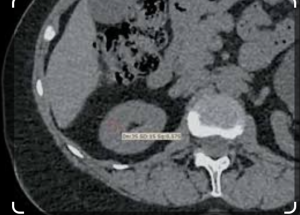

Помимо сегментации, для проведения дальнейших расчетов проводились три измерения плотности паренхимы в области полюсов почки и в области ворот каждой почки в нативной фазе (рис. 2).

Методика расчета раздельного вклада почек на основе автоматической сегментации. Для расчета «массы» контрастного препарата, находящегося в паренхиме почки в конкретный временной момент (в нефрографическую фазу), на основе произведения вычисленного объема паренхимы (V) и ее средней плотности (HU), безусловно целесообразно учитывать плотность паренхимы при нативном сканировании. Для этого из данных о средней плотности, полученных в ходе автоматической сегментации в нефрографическую фазу (HU), вычитали среднее арифметическое трех измерений плотности паренхимы, полученных в нативную фазу (HU 1 , HU2 , HU3).